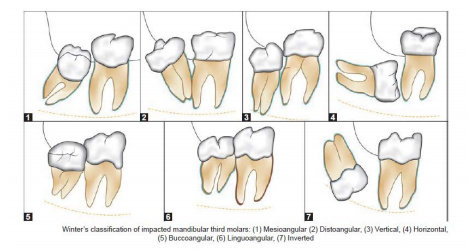

Apa yang dimaksud dengan impaksi gigi? - Ilmu Kedokteran Gigi - Dictio Community

Apa yang dimaksud dengan impaksi gigi? - Ilmu Kedokteran Gigi - Dictio Community

BAB 2 TINJAUAN PUSTAKA 2.1 Definisi Gigi Impaksi Gigi impaksi merupakan gigi yang tidak dapat muncul sepenuhnya ke dalam rongga

PDF) Klasifikasi Impaksi Gigi Molar 3 / Gigi Bungsu | http://adifkgugm.blogspot.co.id/ | Dokter Gigi - Academia.edu

PDF) Klasifikasi Impaksi Gigi Molar 3 / Gigi Bungsu | http://adifkgugm.blogspot.co.id/ | Dokter Gigi - Academia.edu